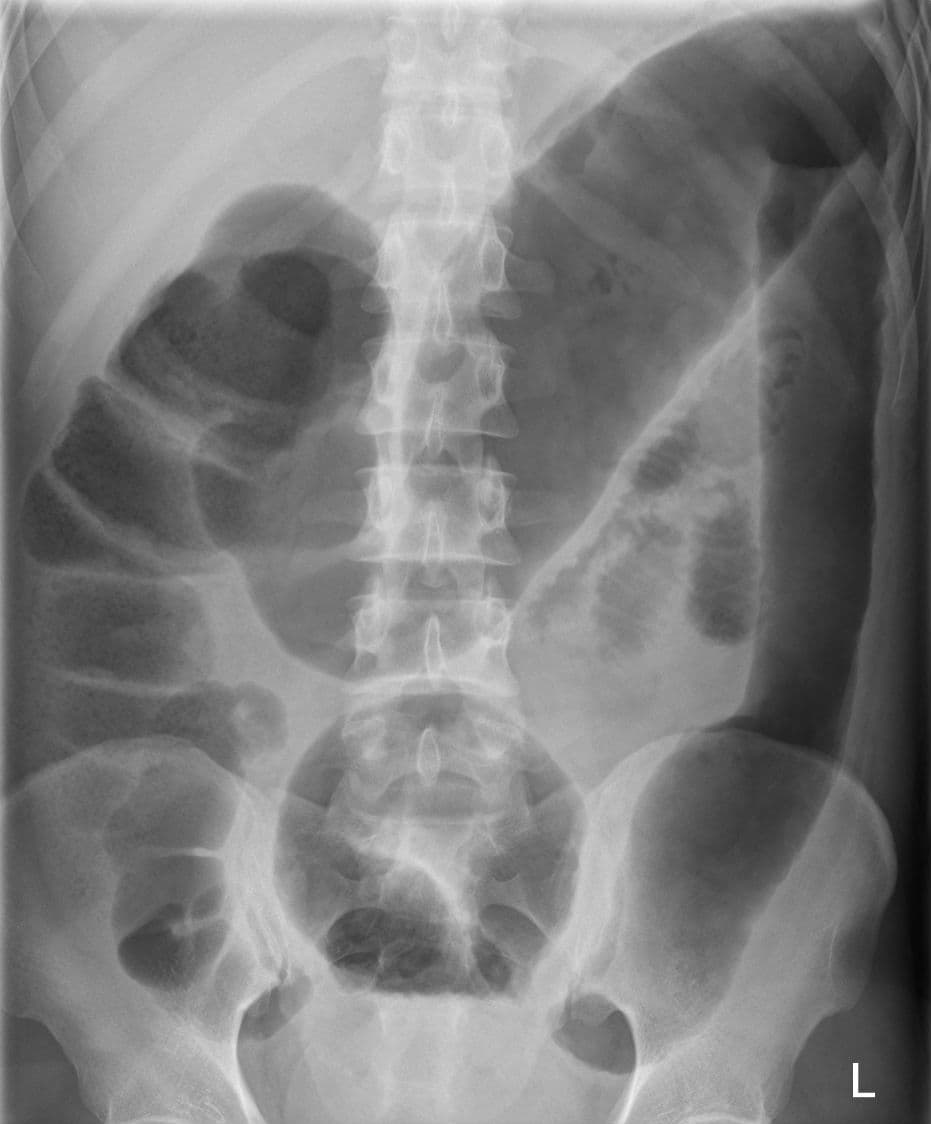

Megacolon is an abnormal dilation of the colon (also called the large intestine). This leads to hypertrophy of the colon. The dilation is often accompanied by a paralysis of the peristaltic movements of the bowel. In more extreme cases, the feces consolidate into hard masses inside the colon, called fecalomas (literally, fecal tumor), which can require surgery to be removed. A human colon is considered abnormally enlarged if it has a diameter greater than 12 cm in the cecum (it is usually less than 9 cm), greater than 6.5 cm in the rectosigmoid region and greater than 8 cm for the ascending colon. The transverse colon is usually less than 6 cm in diameter. A megacolon can be either acute or chronic. It can also be classified according to cause. External signs and symptoms are constipation of very long duration, abdominal bloating, abdominal tenderness and tympany, abdominal pain, palpation of hard fecal masses and, in toxic megacolon, fever, low blood potassium, tachycardia and may lead to shock. Stercoral ulcers are sometimes observed in chronic megacolon, which may lead to perforation of the intestinal wall in approximately 3% of the cases, leading to sepsis and risk of death. Congenital or aganglionic megacolon Medication Acquired megacolon, of which there are several possible causes: Idiopathic megacolon Toxic megacolon Megacolon secondary to infection Clostridium difficile Trypanosoma cruzi (Chagas disease) Pheochromocytoma, possibly secondary to its presenting constipation. Other neurologic, systemic and metabolic diseases Also called Hirschsprung's disease, it is a congenital disorder of the colon in which nerve cells of the myenteric plexus in its walls, also known as ganglion cells, are absent. It is a rare disorder (1:5 000), with prevalence among males being four times that of females. Hirschsprung's disease develops in the fetus during the early stages of pregnancy. A genetic predisposition to Hirschsprung's disease has been linked to chromosome 13 where a missense mutation at an ultraconserved region impairs functionality of the W276C receptor.